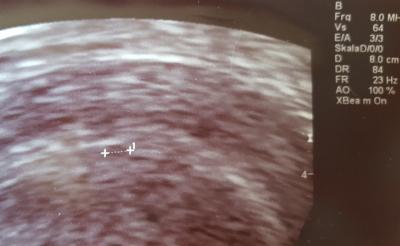

Hi ihr lieben. Es ist unglaublich...Ich hatte meinen bt und bin immernoch sowas von unentspannt,das ist der wahnsinn :-( Nach unsere 1.ivf hatte ich nun am 30.einen positiven hcg wert. 116!! Da Montag ein Feiertag war,konnte ich erst heute zum FA. Schlimm dieses warten!! Er hat einen Ultraschall gemacht,konnte aber nur eine fruchthöhle erahnen(siehe Bild). Ist das normal? Ich kann mir denken,dass noch nicht viel zu sehen ist...Aber was genau bei ca 4+4?? Es wurde auch nochmal Blut abgenommen und morgen wieder zum Vergleich...Ich bin total nervös und muss immer daran denken!! Ich mach mich selbst ganz kirre!! Liebste grüße

Bild zu Nach positiven BT immernoch nervös und ägstlich! - Kinderwunschbehandlung